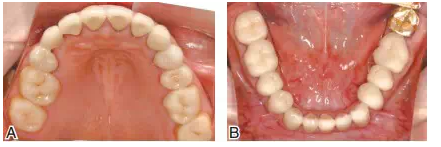

圖16雕刻下頜診斷蠟型(A),翻制下頜暫時冠并戴入口內(nèi)(B)。調(diào)整咬合接觸,暫時冠戴用兩個月,患者無顳下頜關(guān)節(jié)和咀嚼肌系統(tǒng)不適,并能確認(rèn)最適下頜位后,制作最終修復(fù)體

圖17雙側(cè)上頜后牙采用全瓷嵌體(CAD/CAM,eMax,Vivodent Ivoclar),其他基牙采用金合金烤瓷冠修復(fù)。A上頜后牙的高嵌體基牙預(yù)備;B后牙的工作模型;C后牙全瓷高嵌體粘接中,氫氟酸酸蝕,樹脂粘接水門汀粘固

圖18修復(fù)完成后的上下頜咬合面觀